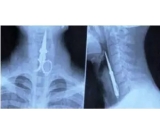

一直都觉得生命很脆弱,但事实告诉我们,生命其实异常的很顽强……1.这个哥们儿在洗牙时,因为朋友讲的笑话太好笑,把一把剪刀吞了下去……2.该病患在手术之后经常觉得腹痛,回...